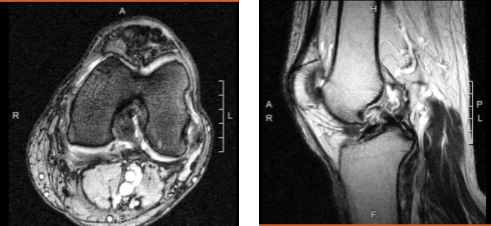

The patient is a 60-year-old guy who has seen a doctor several times for pain on the inner side of his left knee, as well as buckling and giving way. We performed an MRI, which revealed a medial meniscus rupture as well as a partial high-grade ACL tear.

Magnetic resonance imaging of the left knee